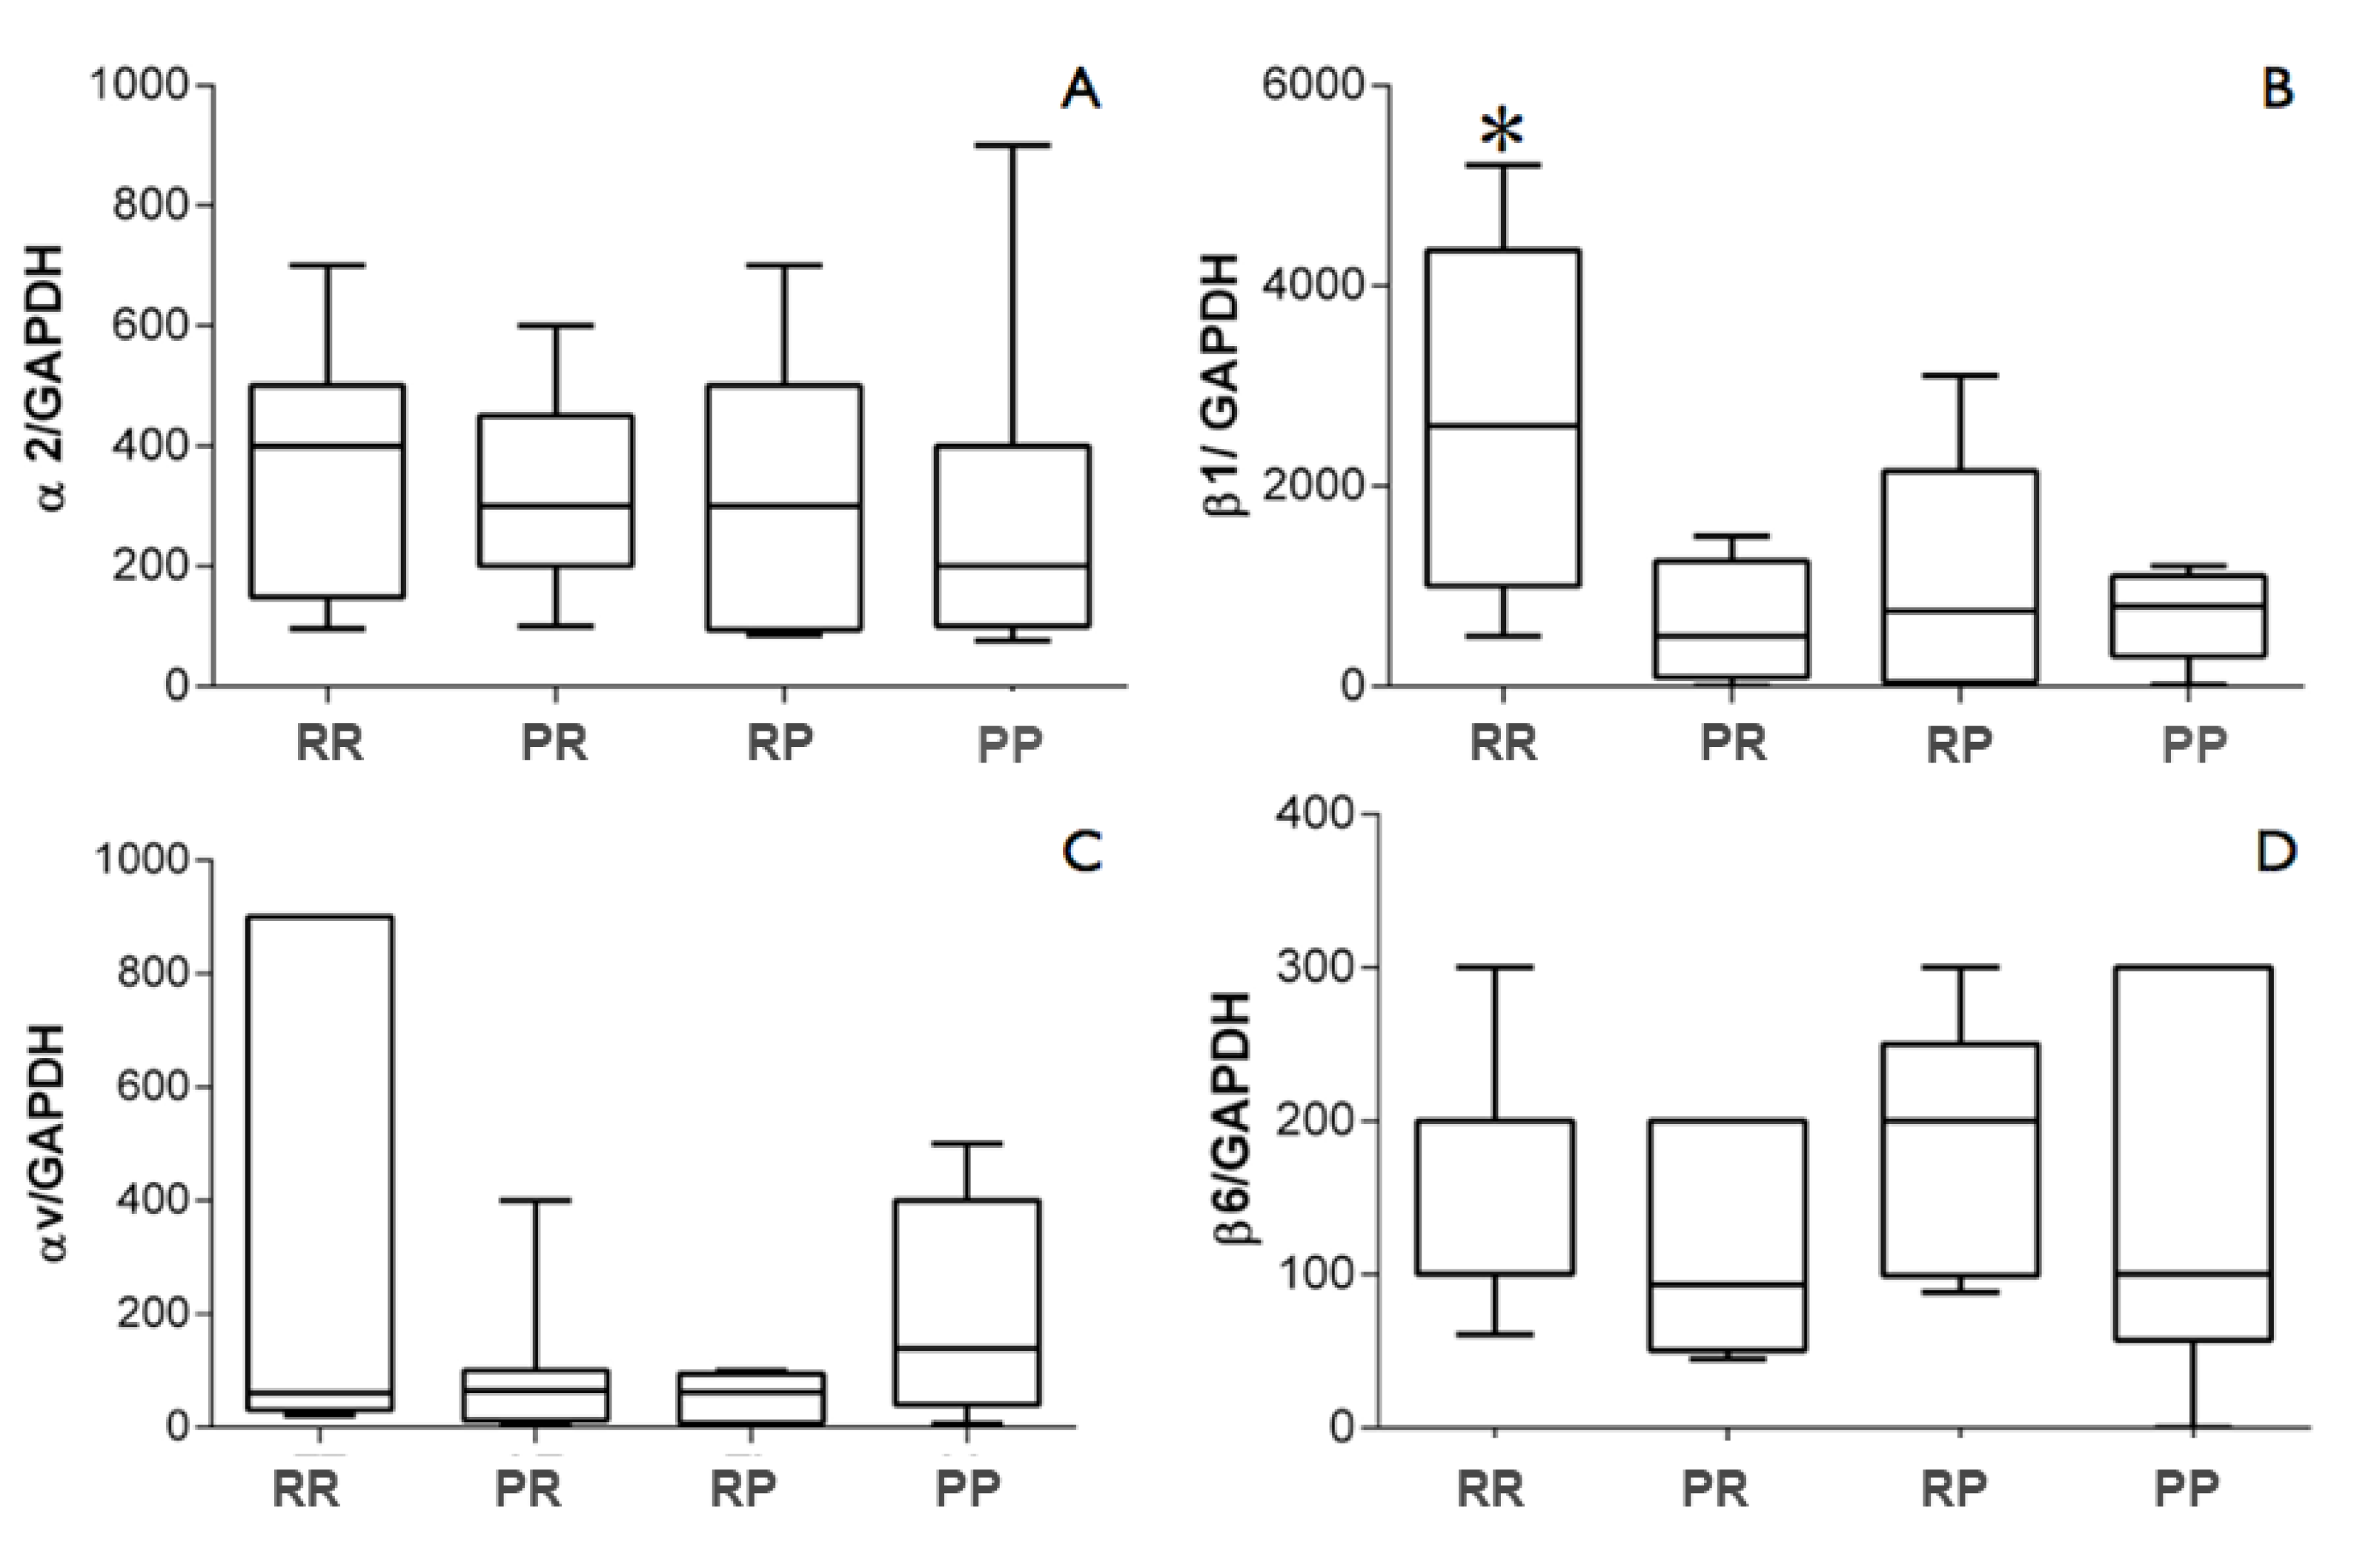

3. Results

4. Discussion

5. Conclusions